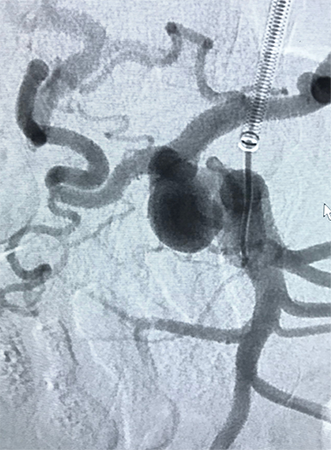

Cirurgia de Aneurismas Periféricos

Assim como na aorta, os aneurismas podem acometer outras artérias do corpo humano. Nos membros inferiores, o aneurisma mais frequente é o que acomete a artéria poplítea, localizada atrás da articulação do joelho. Os aneurismas também podem acometer vasos viscerais como artérias esplênicas, mesentéricas ou renais. O problema pode ser solucionado tanto por técnica endovascular como por cirurgia, de acordo com as características de cada caso.